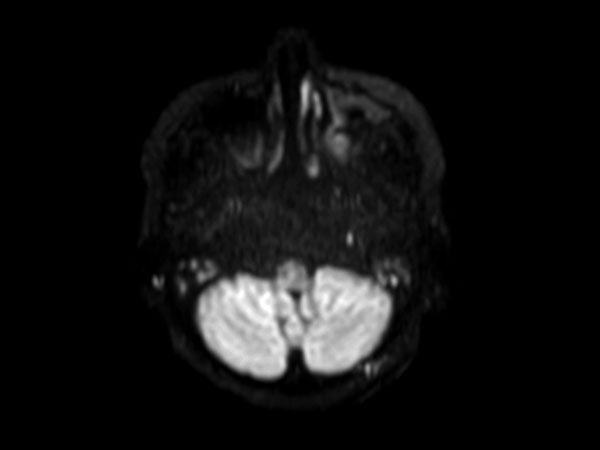

Axial DWI EPI (b1000)